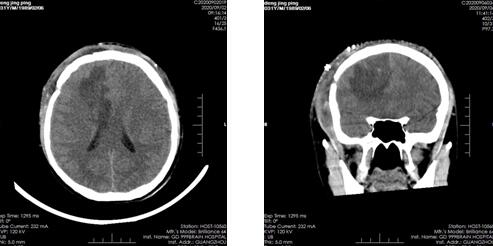

邓先生是一位脑出血患者,家属代诉2020年8月22日突发头痛、头晕、呕吐并左侧肢体偏瘫,遂急送至当地医院行CTA示:右侧额顶叶大量脑出血,中线左移。8月26日于当地医院全麻下行脑内血肿清除术,术中有见病损(具体不详)并切除,术后予以止血、护脑、抗癫痫等对症支持治疗。患者术后生命体征平稳,仍神志不清,查体欠合作,为求进一步诊治,转院至广东三九脑科医院。